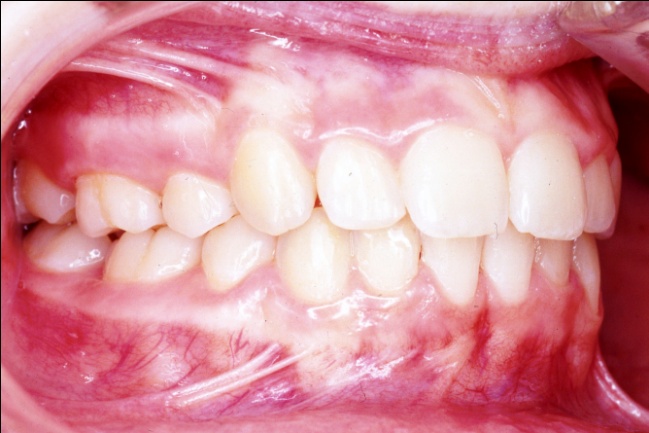

2 - Quand l’orthodontie redessine le visage

Avant traitement, le sourire de profil montre des dents projetées hors de la cavité buccale, avec une incompétence labiale marquée et un profil cutané présentant une biprochélie importante associée à un angle nasolabial très fermé. Après traitement, la transformation est spectaculaire : les dents sont repositionnées dans la bouche, les lèvres se ferment naturellement au repos, le profil est harmonisé, moins protrusif, et l’angle nasolabial a retrouvé une ouverture normale.